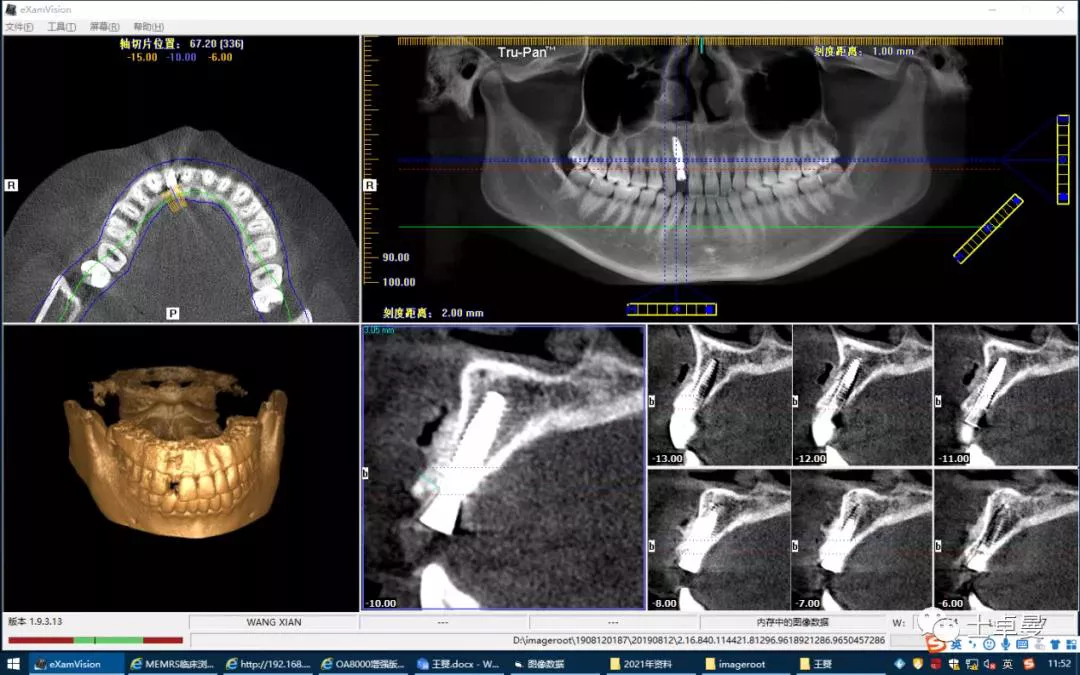

·        CBCT显示种植体三维位置良好;

术后 CBCT 显示种植体三维位置良好

术后一年的CBCT

术后三年的CBCT

不同时期CBCT截图